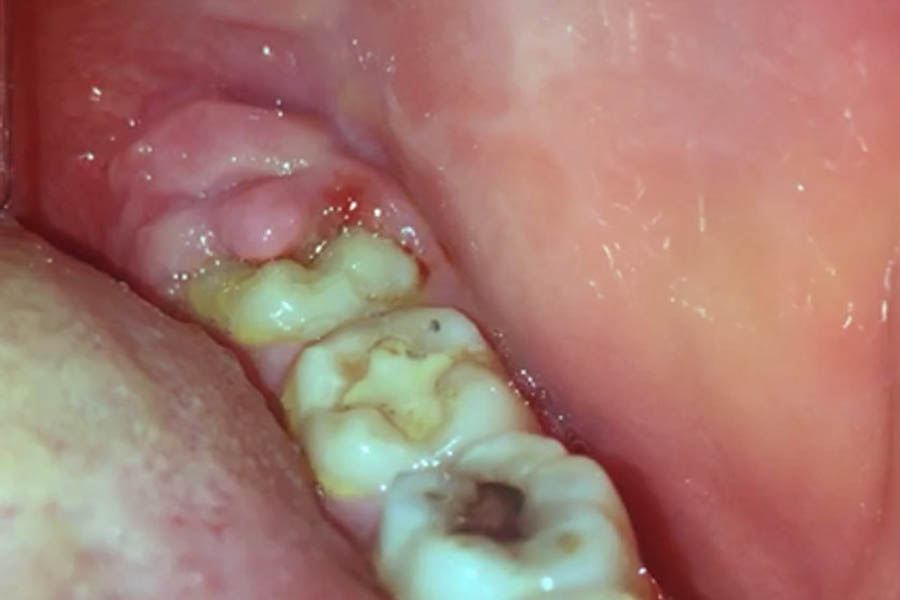

La comparsa dei denti del giudizio è un processo naturale legato alla crescita e allo sviluppo della mandibola. Non sempre emergono contemporaneamente, e in alcuni casi restano parzialmente o completamente inclusi nell’osso. Questo avviene perché la bocca moderna tende a essere più piccola rispetto al passato, creando una sorta di “lotta per lo spazio” tra gli ultimi molari e quelli già presenti. La pressione che si genera durante la loro eruzione può provocare dolore, gonfiore o sensibilità gengivale, fenomeni comuni che non devono allarmare se lievi e transitori.

Sebbene molti denti del giudizio emergano senza complicazioni, esistono segnali che indicano la necessità di una valutazione professionale. Dolori persistenti, difficoltà a aprire completamente la bocca, infiammazioni ricorrenti o mal posizionamento dei denti vicini possono richiedere un intervento. La valutazione da parte di un dentista, spesso supportata da radiografie, permette di capire se i denti stanno seguendo un percorso corretto o se il loro posizionamento può creare problemi a lungo termine.

La gestione dei denti del giudizio varia da persona a persona. In molti casi, la semplice igiene orale accurata e controlli periodici sono sufficienti per evitare disturbi. Spazzolatura regolare, uso del filo interdentale e risciacqui con soluzioni delicate aiutano a mantenere gengive e denti sani. Quando i denti del giudizio crescono storti, provocano dolore o favoriscono infezioni, il dentista può consigliare l’estrazione. Oggi la procedura è sicura e molto più rapida rispetto al passato, riducendo i tempi di recupero e i rischi di complicazioni.